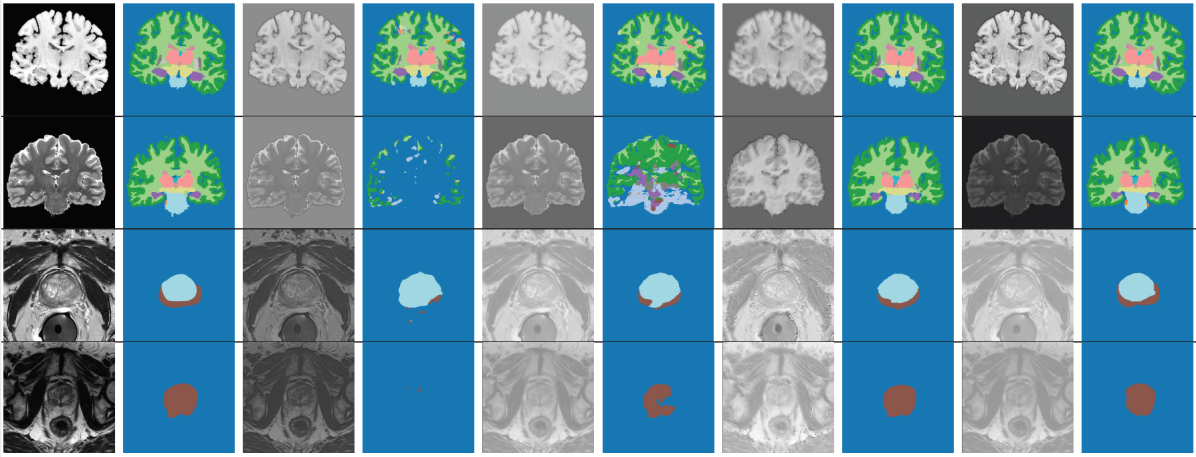

4.4.3 Test-Time Adaptation

For the proposed method, we first trained segCNN on the SD along with DA. Then, we adapted the I2NI CNN, , for each test image, according to the proposed framework. It can be seen that the test-time adaptation provided substantial performance gains over competing methods across all datasets for brain and prostate anatomies. Qualitative results shown in Fig 3 reveal similarly substantial improvements over ’SD + DA’, especially for the brain and prostate datasets. It can be seen that the test-time adaptation improved the predicted segmentation by, for instance, correcting predictions that are contextually misplaced, completing organ shapes and removing outliers. For the cardiac dataset, we observed that the SD training along with data augmentation already provided a fairly good segmentation. The proposed method preserved this performance, but could not further improve it. The improvement in Dice scores with the proposed method as compared to post-processing using the trained DAEs (SD + DA + Post-Proc.) was statistically significant for 3 out of the 5 datasets (marked with * in the Table), as measured using a paired Permutation test with 100000 permutations. For the other datasets, we obtained similar results upon direct post-processing as with the test-time adaptation using DAEs.